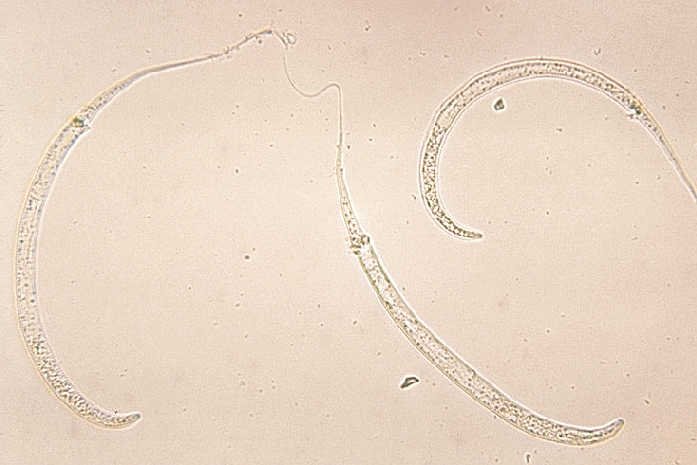

Robak jest idealnie przystosowany do pasożytowania na ludziach. Jego larwy czekają na swoje ofiary w mikroskopijnych skorupiakach (widłonogach), żyjących w wodzie. Po wypiciu takiej wody, Dracunculus medinensis rozwija się w człowieku i tam rozmnaża przebijając się potem przez układ pokarmowy. Samice, które dorastają do metra długości, schodzą potem najczęściej do nóg, i tam przebijają się. Pasożyt powoduje ogromny ból podczas przemieszczania się pod skórą (może on wyłączyć człowieka z życia – pracy czy nauki – na nawet trzy miesiące). Innymi utrudniającymi życie objawami są gorączka, nudności i wymioty. Rana po przebijającej się samicy może też zostać zakażona innymi bakteriami. By złagodzić ból, ludzie często chłodzą ranę w wodzie, gdzie pasożyt może roznieść kolejne pokolenie. I cykl się zamyka.